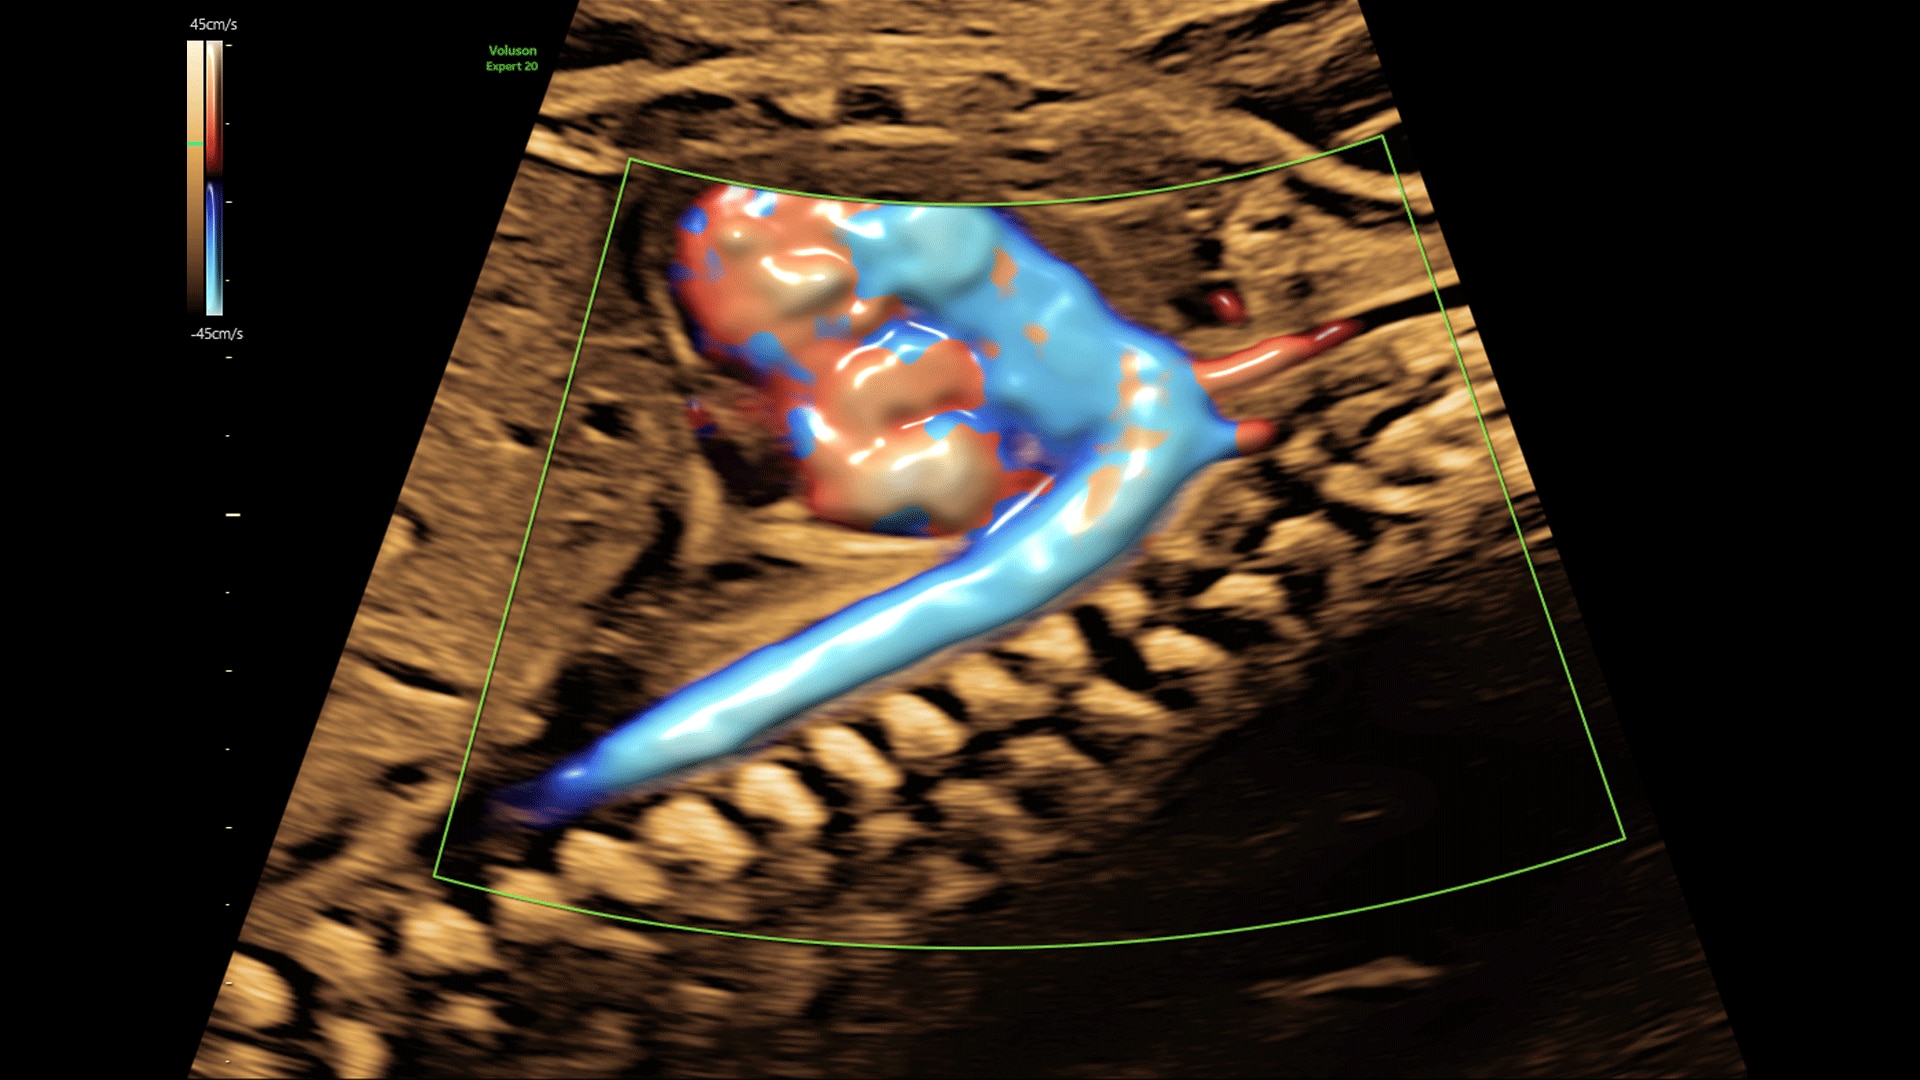

Amplify imaging performance and simplify scanning with our most advanced architecture

Extraordinary clarity and definition so you can focus on early detection and intervention.